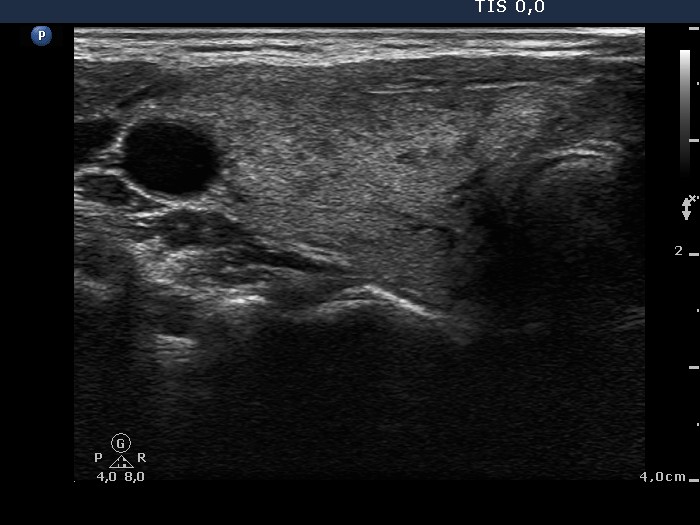

Follow-up investigation 36 months after first visit (ultrasonographic picture 1)

Patient on daily 10 mg methimazole therapy in euthyroid state

Right lobe, transverse scan. Only small moderately hypoechogenic areas are found.